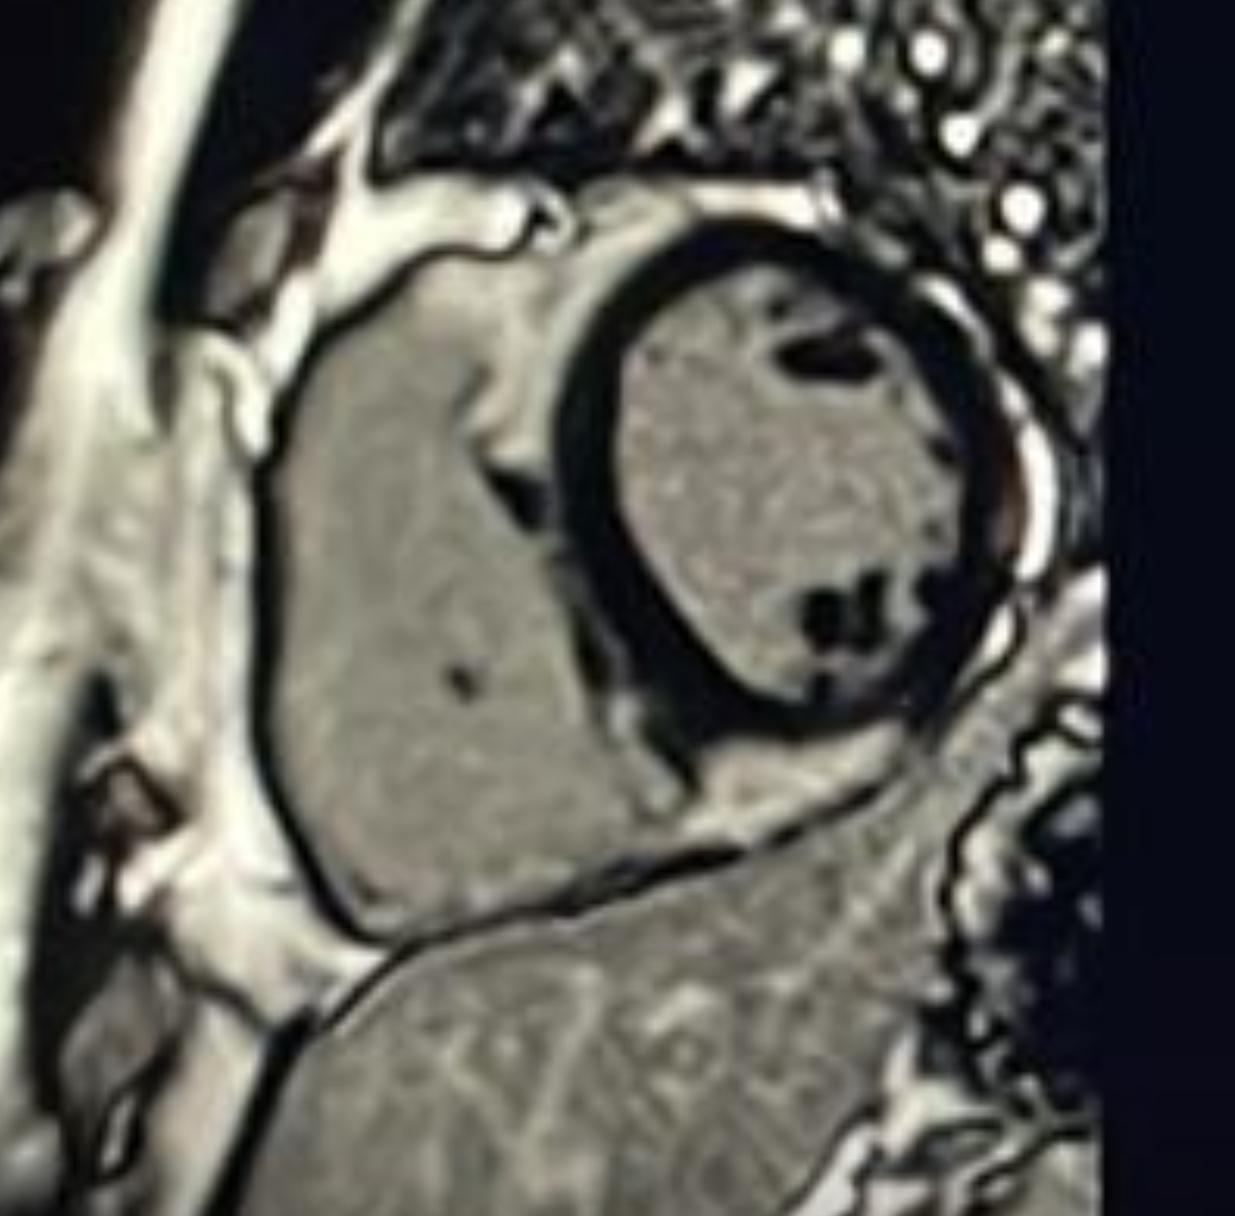

Late Gadolinium Enhancement sequences (Short axis)

Hook Sign